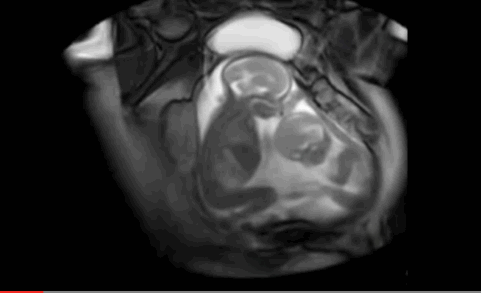

这是核磁扫描,呈现白色的是羊水,我们可以清晰的看到两个宝宝。